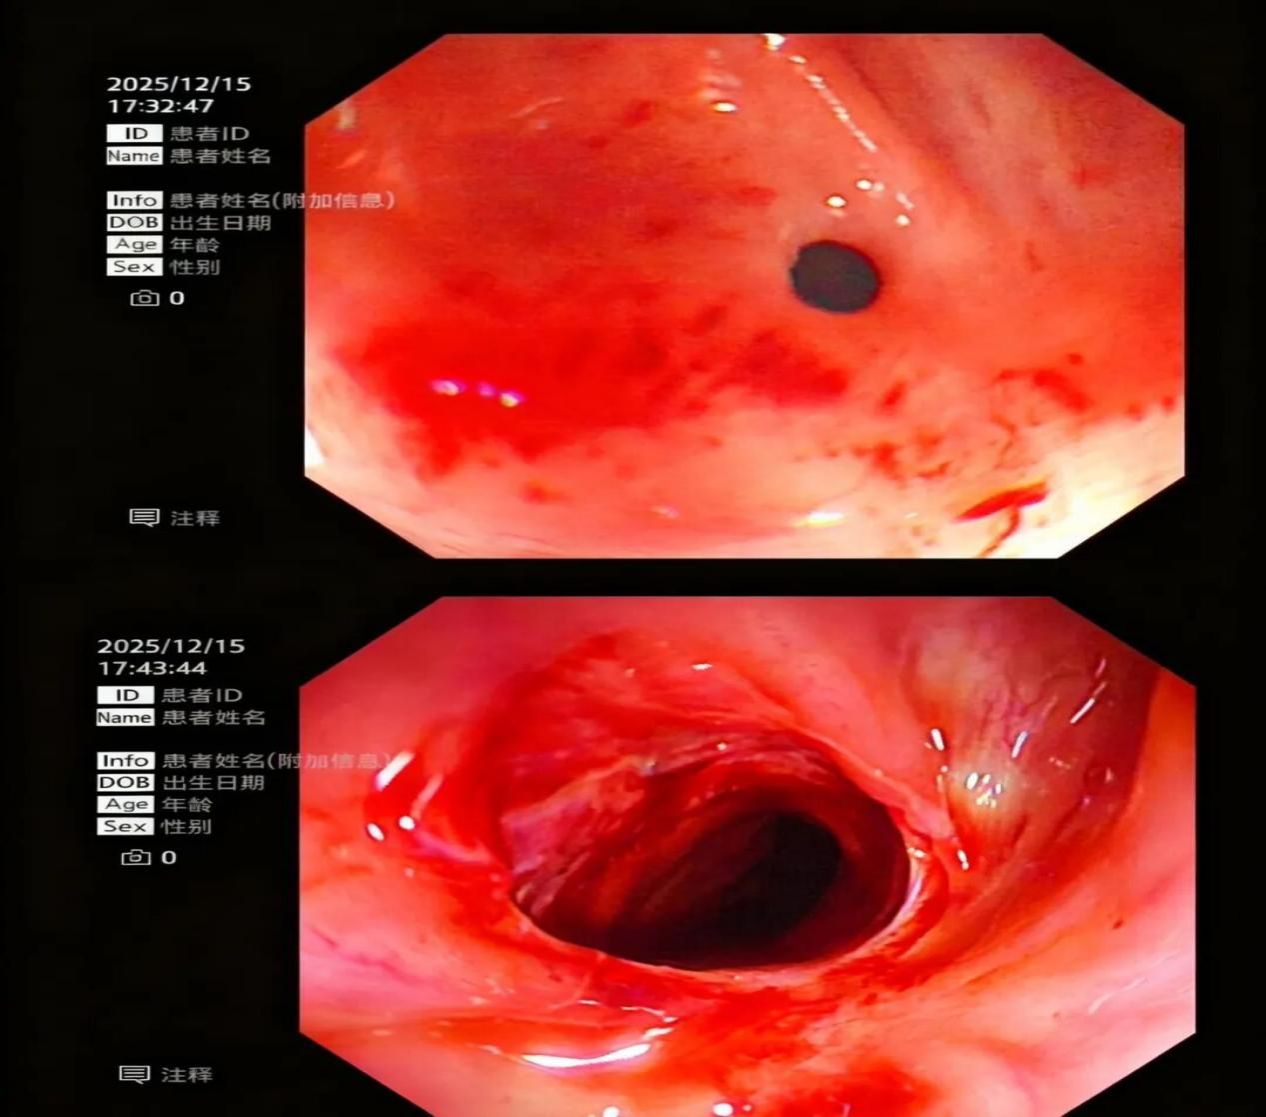

6、新疆医院首例食管胃吻合口狭窄球囊扩张术圆满成功

12月15日,消化科驻疆专家万晓龙主任领衔团队,成功为食管癌术后吻合口狭窄患者实施内镜下球囊扩张术(EBP)。这是新疆医院首例消化道狭窄微创介入手术,不仅为患者重建了进食通路,标志着新疆医院在消化内镜微创治疗领域实现"零的突破"。